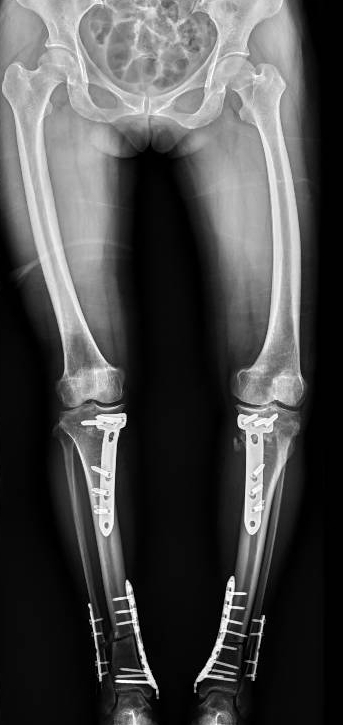

李彬在詳細(xì)了解了董阿姨的病史、進(jìn)行了全面的體格檢查和相關(guān)的輔助檢查后,組織科室進(jìn)行了深入的討論。最終的“答案”是——雙膝骨性關(guān)節(jié)炎、雙膝關(guān)節(jié)畸形、骨質(zhì)疏松以及雙膝半月板損傷。

面對這樣復(fù)雜且嚴(yán)重的病情,李彬并沒有退縮。他深知,對于董阿姨來說,這不僅僅是一次手術(shù),更是一次重生的機(jī)會。因此,他精心制定了手術(shù)方案:對雙下肢脛骨近端、遠(yuǎn)端以及雙側(cè)腓骨遠(yuǎn)端進(jìn)行截骨矯形,并進(jìn)行植骨內(nèi)固定。這樣的手術(shù)方案,無疑是對醫(yī)生技術(shù)的一次高難度挑戰(zhàn)!

手術(shù)前 手術(shù)后

2024年8月13日,手術(shù)順利進(jìn)行。

手術(shù)很成功!經(jīng)過精心的治療和護(hù)理,董阿姨在9月順利出院。當(dāng)她再次站在鏡前時,她驚喜地發(fā)現(xiàn)自己仿佛長高了一截,那份曾經(jīng)讓她備受折磨的疼痛與不適也逐漸消失了。